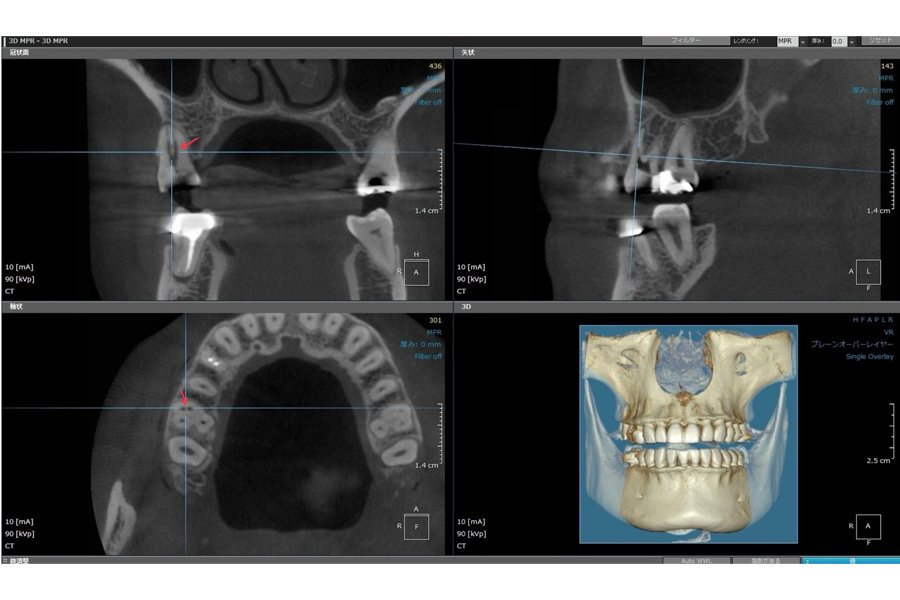

歯科用CTによる

高精度な診断と治療

当院では、歯科用CTを活用した精密な診断により、治療の成功率を高めています。CT撮影によって、顎の骨の立体的な形状や歯と神経の位置関係、骨の密度までを詳細に把握することができ、事前に正確な治療計画を立てることが可能となります。

特に、歯の根の中にある複雑な形態の「根管」に対しては、CT画像によってその構造を三次元的に確認できます。たとえば、肉眼では見えない根管の存在や根管の枝分かれなどの複雑な走行、副鼻腔炎との関連性、根の先端に膿が溜まっているかどうかなど、目視では判断しにくい病巣の状態も、明確に把握できます。

また、当院の精密根管治療(マイクロスコープ根管治療)においては、この歯科用CT撮影を必須としています。的確な診断をもとに、より確実で安全な治療を行うためには欠かせない工程です。

なお、歯科用CTの撮影は保険適用範囲内で対応可能ですので、費用面でも安心してご利用いただけます。

歯科用CT

歯科用CTは、根管の数や形態、根尖病変の範囲を三次元的に把握することができます。両方使うことで、今までわからなかった問題や見えなかった感染源に対してアプローチすることが可能となります。